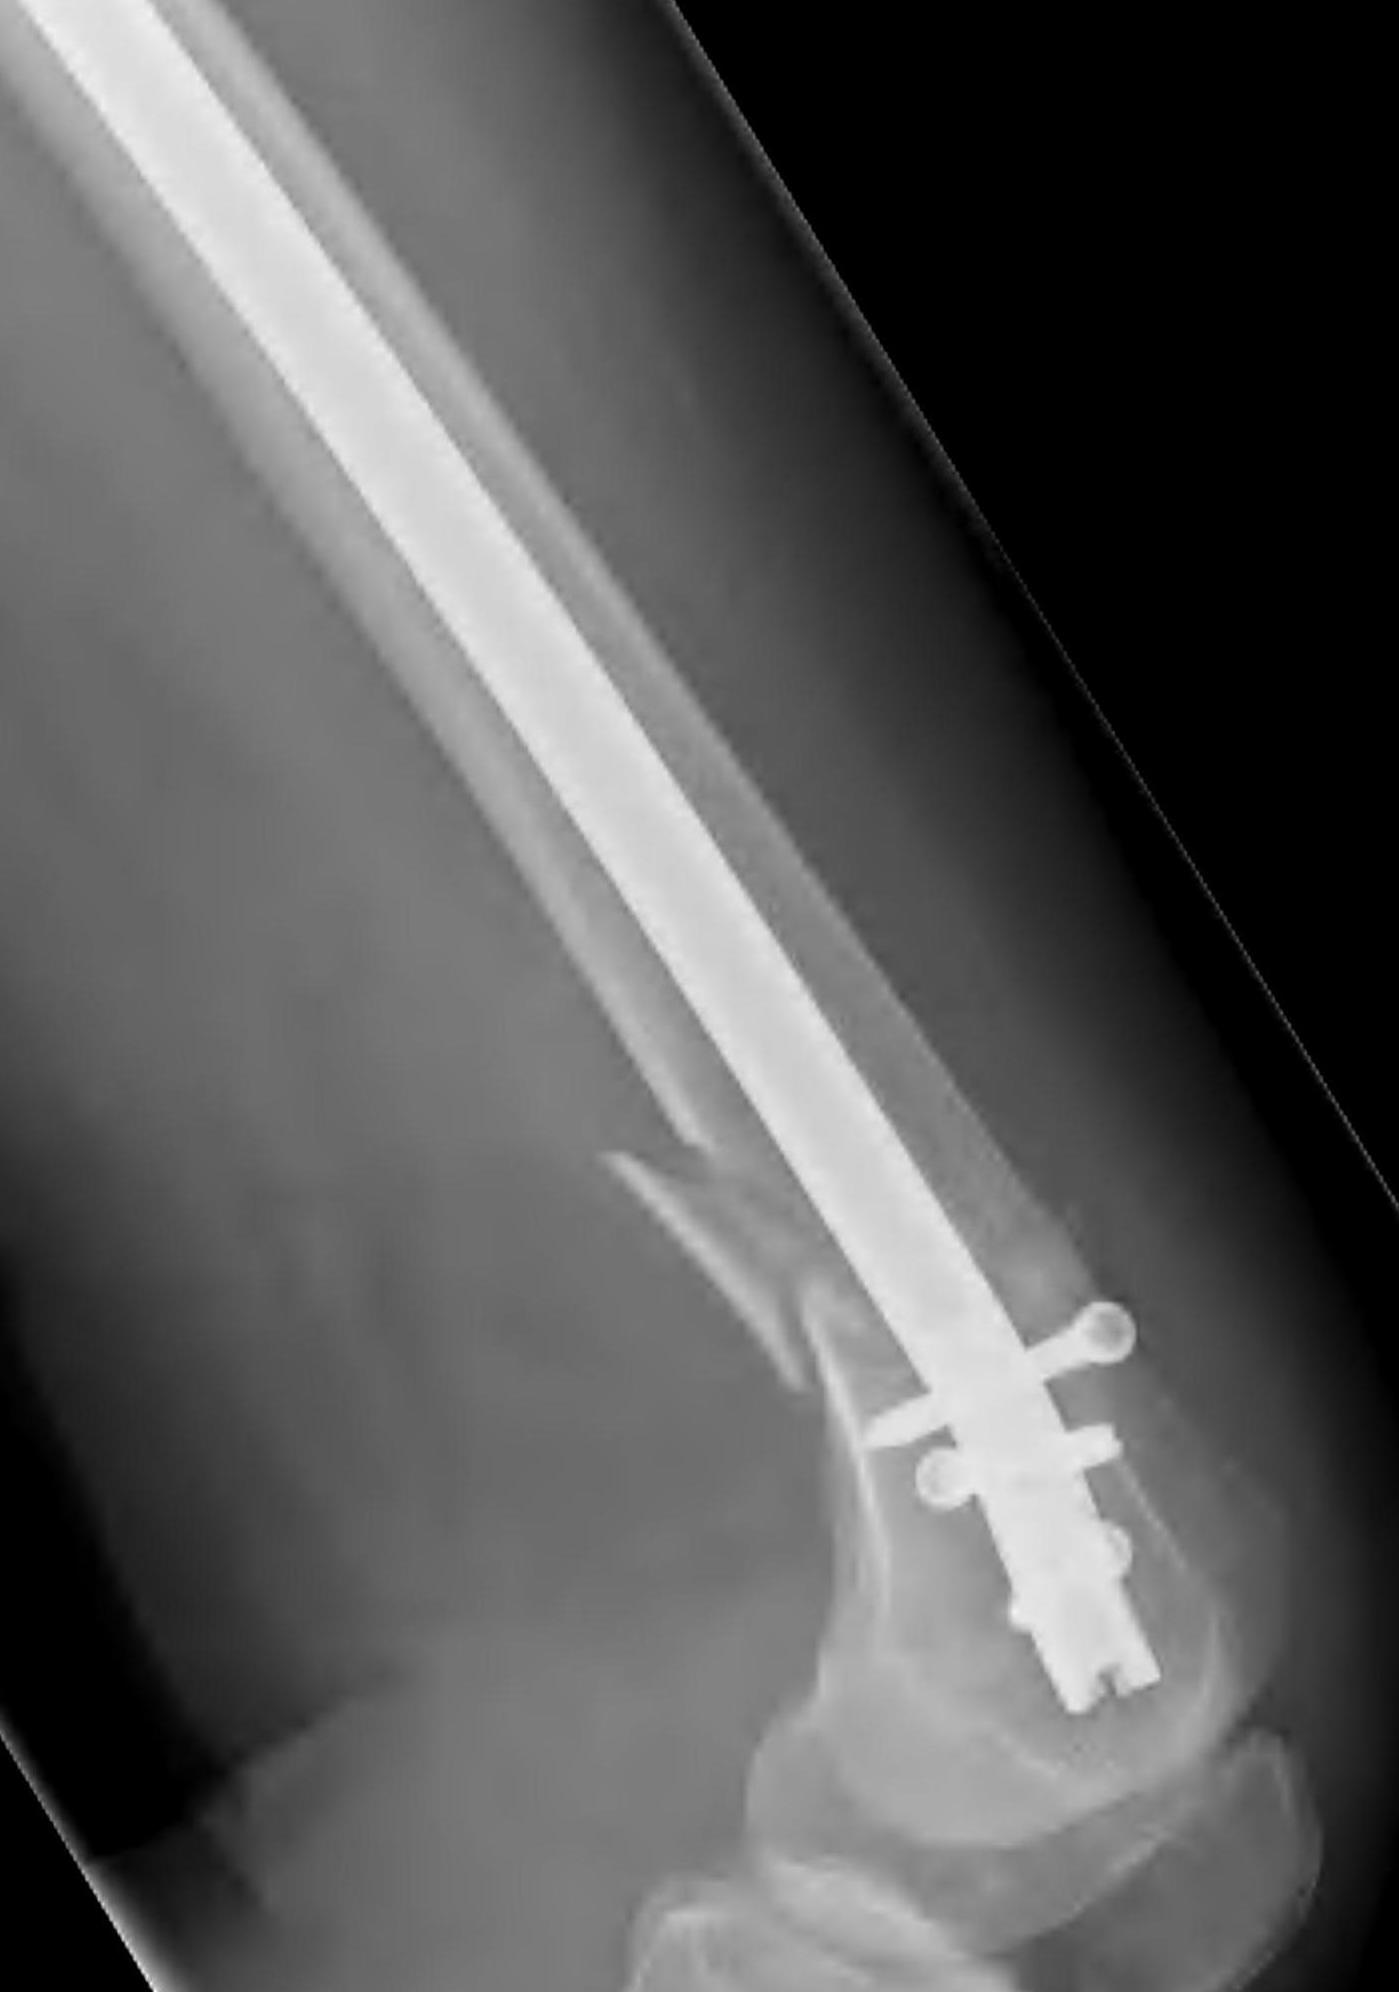

Lateral Plate

Surgical Technique

Position

- patient supine on radiolucent table with image intensifer

- elevate femur to obtain lateral image without interference from other leg

- flex knee to detension gastrocnemius, aiding fracture reduction

Approach

A. Lateral anterolateral approach

- longitudinal incision over lateral distal femoral condyle

- split ITB

- elevate vastus lateralis and cauterize perforators

Apply plate distally

- length, valgus alignment, rotation restored

- ensure screws not in joint / above blumensaat's

- ensure screws not in PFJ (distal femur is trapezoidal)

MIPO plate technique

- percutaneously elevate muscle off femur with elevator

- insert appropriate length plate (4 bicortical screws above)

- second proximal incision

- obtain indirect reduction

- attach plate with screws